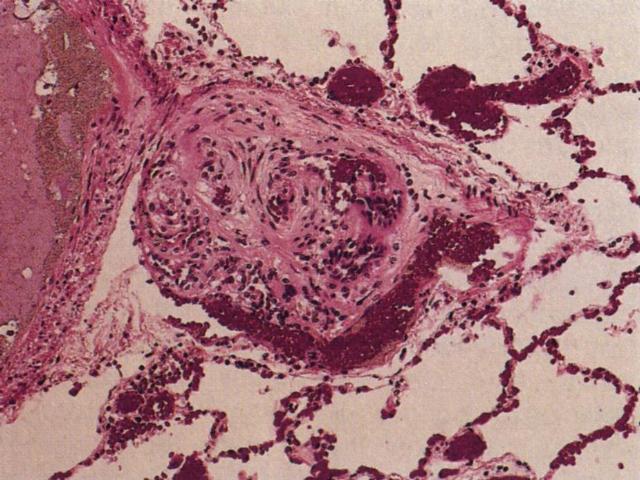

El Tromboembolismo pulmonar (TEP) es una patología frecuente del pulmón. El TEP es una secuencia de eventos que comienza con la formación de trombos en órganos a distancia conectados al pulmón por circulación venosa. Es importante mencionar que el pulmón es el único territorio capilar que recibe circulación venosa en forma aferente, por lo que cualquier trombo generado en distintos órganos tiene el riesgo potencial de afectar el capilar pulmonar. La migración del trombo al pulmón se llama embolo y de ahí el término trombo-embolismo pulmonar. La principal causa de TEP es la trombosis venosa profunda. Esta y otras causas de TEP se muestran en la figura [imagen]. Como se observa diversas causas además de la trombosis pueden ser causa de TEP como por ejemplo la embolía de líquido amniótico o la embolia grasa [imagen].. La gran mayoría de los TEP son subclínicos, son microembolías que en forma crónica pueden llegar a provocar Hipertensión Pulmonar. Sólo los TEP masivos pueden provocar sintomatología clínica [imagen]. Los cortes histológicos de esta lesión revelan un trombo organizado compuesto por capas alternadas de eritrocitos y leucocitos / fibrina [imagen]. La consecuencia de esta lesión en el pulmón será la hemorragia [imagen] y el infarto hemorrágico del pulmón.[imagen]